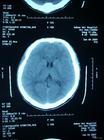

2. 頭顱CT:可顯示腦室腦池變小腦溝變窄。